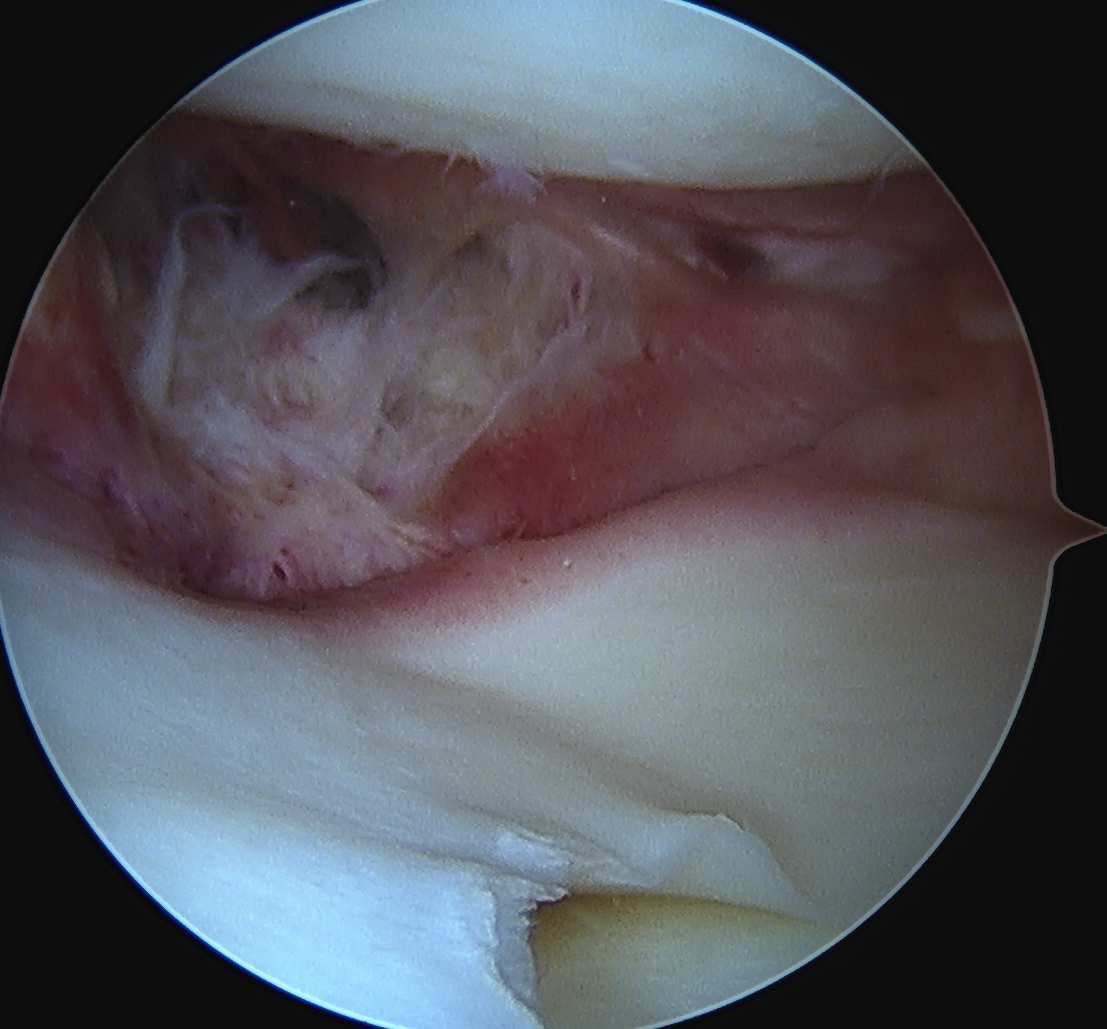

Arthroscopy

Findings

- medial drive through sign

- excessive opening of medial compartment

- may see lift off of the medial meniscus with injury to deep MCL / meniscotibial ligament

- may see injury above medial medial meniscus with injury to deep MCL / meniscofemoral ligament

Meniscotibial ligament injury Meniscofemoral ligament injury